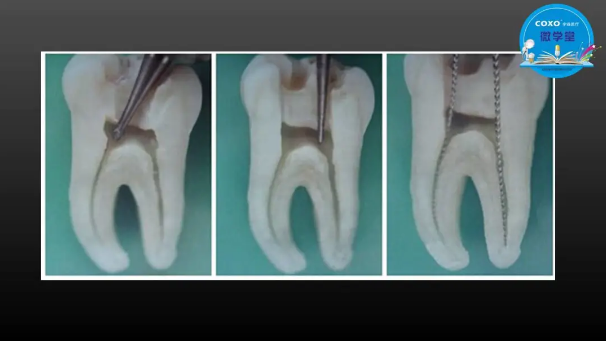

主任醫(yī)師,牙體牙髓副主任, 廣東省口腔醫(yī)院牙體牙髓科 主任醫(yī)師。2003年碩士研究生畢業(yè),研究方向?yàn)檠荔w牙髓病學(xué),擅長(zhǎng)于牙體牙髓病的診斷、齲齒、牙髓炎、根尖周病的治療以及前牙美容修復(fù)。